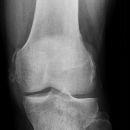

Kniegelenk